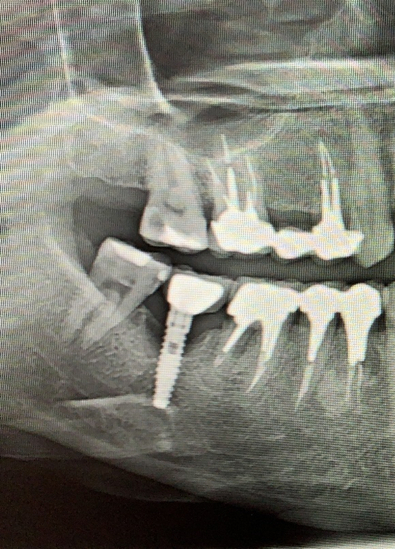

Январь 2023. Произошел спор с пациентом, который 4 месяца назад удалил зубы в городской поликлинике, где ему разворошили всю кость и он был очень удивлен, почему мы не сможем сходу установить импланты без наращивания. Этой ситуацией хотелось с кем-то поделиться, причем с тем, для кого это не рутина. Я вспомнил про свои посты. И меня понесло. Начал писать статьи одну за другой. И в какой-то момент я заметил, что чем больше я пишу, тем больше народ начинает задумываться о своем здоровье. Люди стали засыпать меня вопросами, я по мере возможности отвечал, иногда совсем поражался тем, насколько люди у нас не просвещены в этом плане. Стало поступать множество призывов помочь, просили персональной консультации.

Кидаем снимки, если есть.

Если есть КТ, то кидаем на почту vadbel1310kt@yandex.ru В теме письма указываем ваш никнейм телеграме, чтобы я мог понять кто это прислал, посмотреть и ответить.